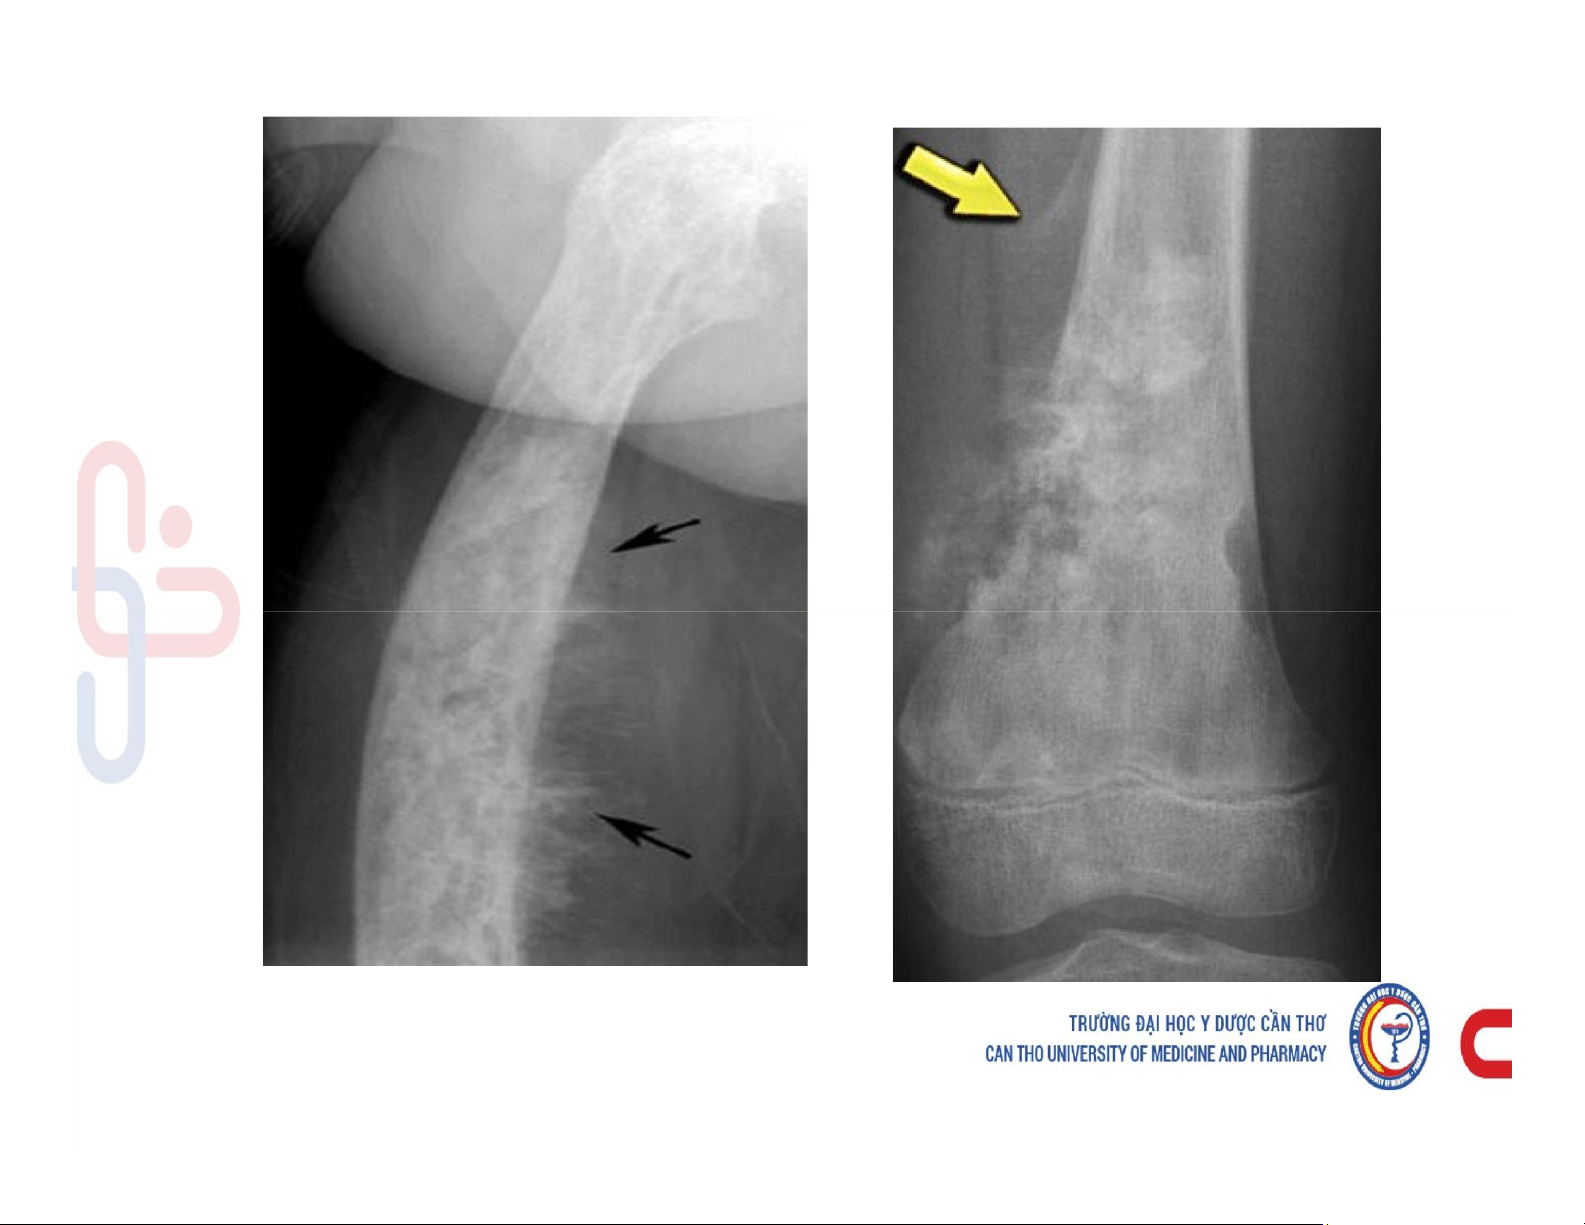

Mô tả và chú thích được các cấu trúc giải phẫu x quang xương khớp. Mô tả các dấu hiệu cơ bản trên phim x quang xương khớp. Phân tích được hình ảnh x quang bệnh lý của một số nhóm bệnh lý xương khớp. Các dấu hiệu cơ bản của phim. Tài liệu giúp bạn tham khảo, ôn tập và đạt kết quả cao. Mời đọc đón xem!